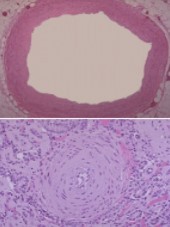

What is seen in vascular histology in scleroderma?

o Top picture is a normal artery with 3 layers

o Bottom picture is a small artery in a patient presenting to A&E with a renal crisis (characterised by very high blood pressure)

§ There is intimal proliferation giving an onion skin appearance

§ Lumen effectively obliterated and some small thrombi for